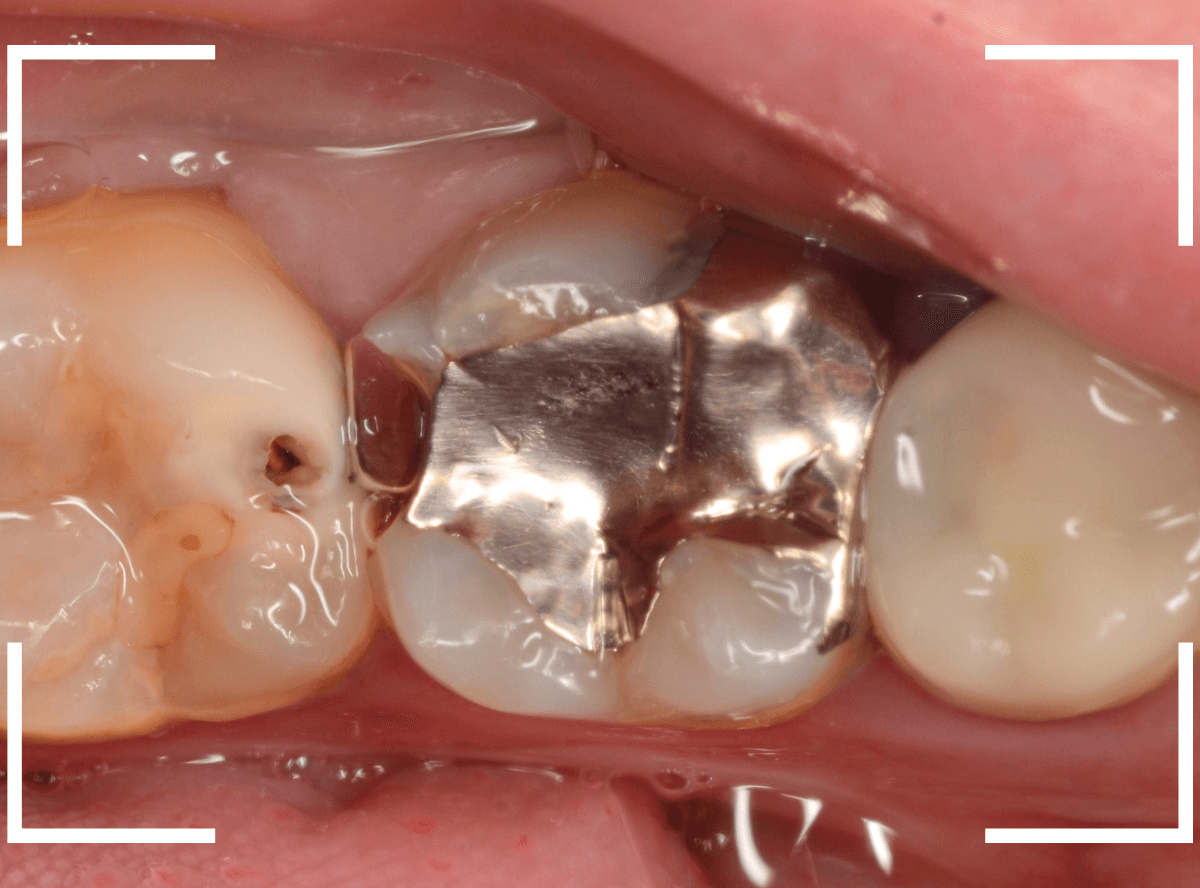

他の虫歯の治療のブログでも紹介した症例を例に紹介します。

歯と歯のすき間が大きな虫歯になっているのが分かります。

金属を外して、ある程度虫歯を除去したところです。